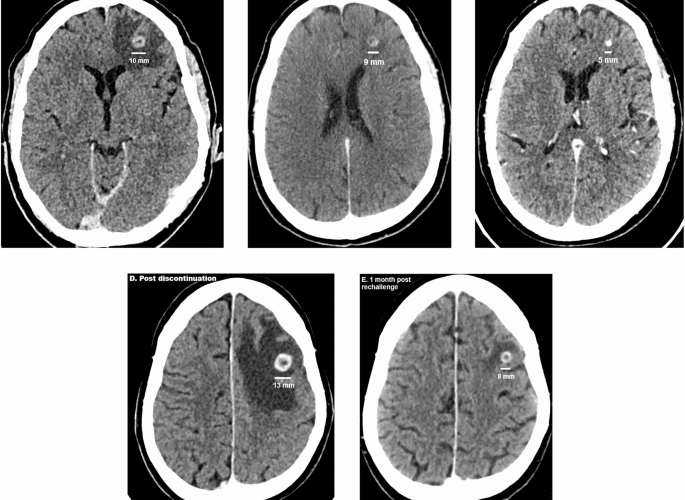

Immuno-molecular features and therapeutic implications of brain metastases in clear cell renal cell carcinoma patients

We start with a case report, because it illustrates well the current challenges and possibilities ...